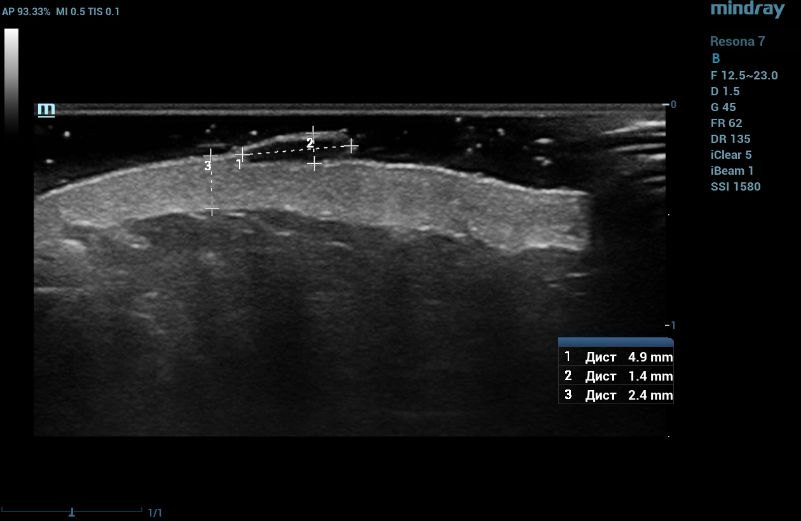

Ultrasound examination of the nevus was performed on the Resona 7 ultrasound machine (Mindray, China) using the high frequency linear transducer L20-5U (max frequency 23 MHz). When the transducer was placed in the projection of the visible nevus of the right zygomatic region of the face, the derma was locally thickened to 2.4 mm due to a hypoechogenic mass located under the epidermis and slightly elevated, spreading in depth to all layers of the dermis with clear rough boundary of heterogeneous echogenicity, without hyperechogenic sports, giving a weak acoustic darkening of the echo signal (Figure 2). Blood flow is not registered inside the nevus in the Color Doppler mode (Figure 3).

Ultrasound examination of the nevus in B mode

Figure 2. Ultrasound examination of the nevus in B mode

Such ultrasound signs are characteristic of compound nevus [2]. A pronounced subcutaneous low-echo band (SLEB) attracts attention (0.9 mm – 50% of the total thickness of the dermis – 1.7 mm), which is the ultrasound sign of facial skin photodamage [3].